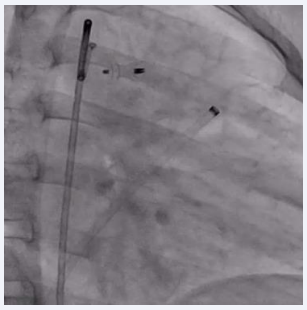

Procedure was done under general anesthesia. Right femoral artery and vein, along with left femoral venous access, were established and 6F sheaths were inserted. A 6F pigtail catheter was advanced through the right femoral artery along the descending aorta up to the PDA defect. An aortic shoot was performed via the pigtail catheter to visualize and confirm the size of the defect. Pressures across the main pulmonary artery (MPA), were recorded using a 6F MPA catheter. A 0.025 mm J-tip Terumo wire was passed through the right femoral vein into the right atrium, followed by the right ventricle, and then into the main pulmonary artery. The MPA catheter was replaced with a 6F Judkins right catheter. Due to the dilated MPA and PDA spasm from repeated attempts to cross the defect, there was difficulty in advancing the terumo wire through the defect. After multiple attempts, the 0.025 mm Terumo wire was successfully passed through the defect and subsequently exchanged for an Amplatzer Super Stiff wire. The ductal spasm led to a possible underestimation of the required device size. A Lifetech CERA 8/6 mm device was loaded onto the device delivery sheath. To facilitate the challenging recrossing, a Mullins long sheath, one size larger than recommended for the Lifetech CERA device, was inserted and advanced up to the defect over the Amplatzer Super Stiff wire. The Super Stiff wire was then exchanged for the Terumo wire, which was snared through the left femoral artery to secure access during the trial of device placement (Figure 2).

Figure 2 Fluoroscopic image showing PDA device inflated across the PDA with the Terumo wire maintained across the defect.

Figure 2: Fluoroscopic image showing PDA device inflated across the PDA with the Terumo wire maintained across the defect.